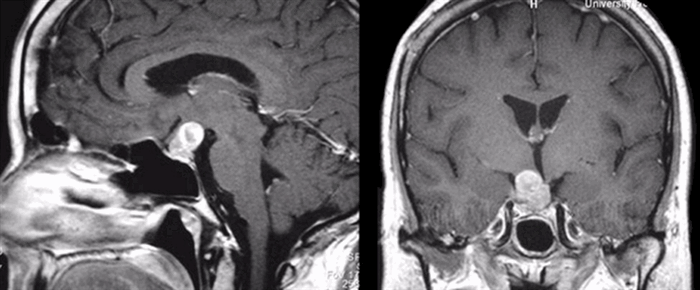

Макроаденома гипофиза на МРТ

По размерам аденомы гипофиза выделяют: микроаденомы (менее 1 см в максимальном измерении); макроаденомы.

Диагностика аденомы гипофиза: тщательные гормональное и офтальмологическое обследования и нейровизуализация. Магнитно-резонансная томография — основной метод диагностики, позволяет выявить аденомы размерами менее 5 мм, однако, даже с учётом этого, примерно у 25–45% пациентов визуализировать аденому не удаётся. Компьютерную томографию применяют только в экстренных ситуациях при невозможности провести магнитно-резонансной томографии для исключения тяжёлых осложнений.

Все опухоли гипоталамо-гипофизарной области в зависимости от размера принято классифицировать на микроаденомы (не более 1,0 см в диаметре) и макроаденомы (диаметром более 1,0 см). В структуре аденом гипофиза лидируют пролактиномы (около половины всех опухолей), на втором месте - гормонально-неактивные аденомы. По размерам преобладают микроаденомы (около 70,0% всех выявленных образований).

При МР-исследовании гипофиза можно получить срезы толщиной около 1 мм, что позволяет выявить даже микроаденомы размером до 2 мм.